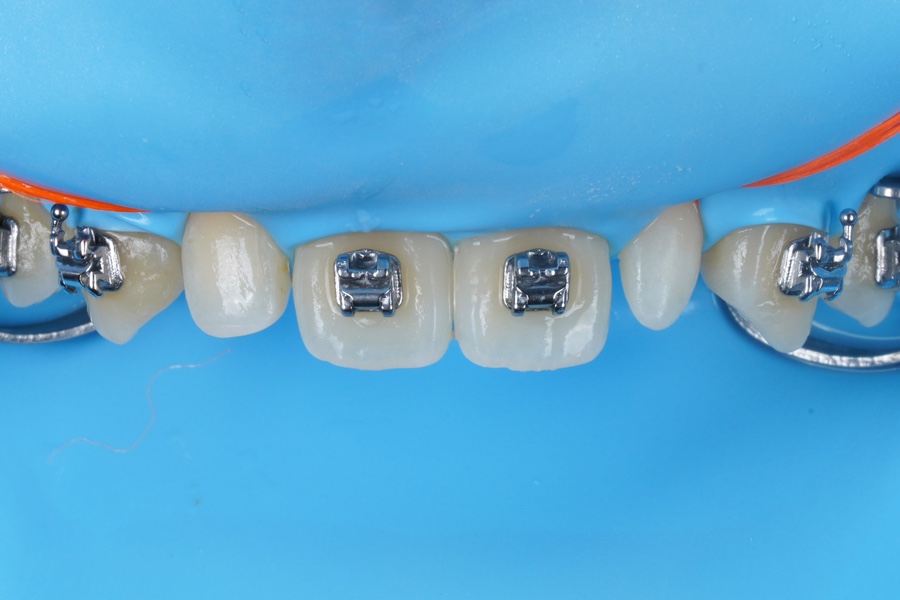

치료는 언제나처럼

러버댐을 거는 것부터 시작합니다.

레진비니어도 레진 접착이고

제가 치아 색상을 맞춰

심미수복용 레진을 한겹 한겹 쌓아올리는

Layering Technique을 써야하니

방습이 중요합니다.

이렇게 대강 형태를 잡아뒀는데요

제가 늘 말씀드리고 강조하는

자연치아가 가진 광학적 특성!

{투명층}

그 투명층의 재현이 잘 되었죠!?

레진으로 투명층을 제가 직접 구현하는 건

상당한 집중력을 발휘해야하는

굉장히 고된 작업입니다..